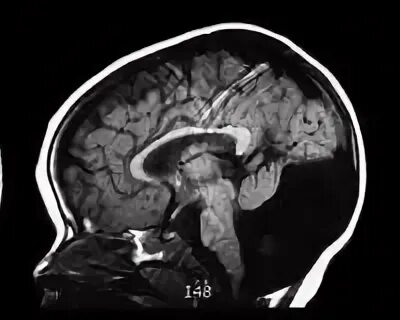

Денди уокера мрт